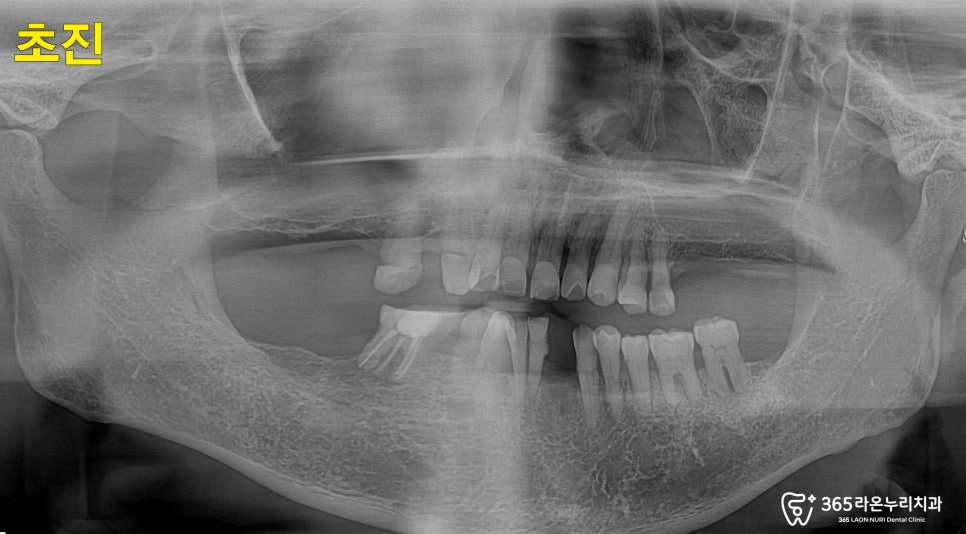

엑스레이를 보시면 전체적으로

치아 뿌리가 드러날 정도의

골소실이 일어나 있는 것을

더욱 명확하게 확인할 수 있었는데요.

보시는 것과 같이

잇몸뼈가 뿌리 끝까지 녹아

더이상 치아를 지지하지

못하고 흔들리고 있었는데요.

이처럼 전체적으로 치아의 상태가 좋지

않았던 곳들은 발치 후 임플란트 식립 및

뼈이식 치료를 진행하기로 결정하게 되었습니다.

치료 전, CT로 남아 있는 뼈의

상태 확인도 잊지 않았습니다.